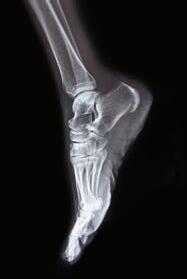

THE WORLD’S #1 IN ORTHOPEDICS IS RIGHT HERE IN CONNECTICUT.

HSS, the world’s #1 in orthopedics, has teamed up with Stamford Health to bring the best comprehensive musculoskeletal care to Connecticut. And with a new location now in Westport , we’re bringing more of our industry-leading experts to support you from diagnosis through nonsurgical and surgical treatment and postoperative care. Now you can choose to move better and get back to doing what you love.

To learn more visit HSS.edu/StamfordHealth